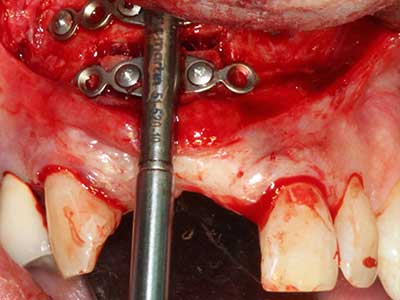

Пиезохирургията има допълнителни предимства при събиране на костни блокове. В допълнение към високата прецизност при остеотомията, описана по-горе, употребата на фините режещи накрайници значително намаляват загубата на материал. Голяма загуба на материал по време на събиране може да се очаква с дебелите накрайници, особено при употреба на борери Линдеман (Lakshmiganthan, Gokulanathan et al. 2012). Базалното разделяне, което е необходимо, особено за присадка на блок при ретромолар, е улеснено от специално създадени правоъгълни триони. В резултат на това, пиезохирургията е разглеждана като прецизна, улеснена и безопасна процедура за събиране на костни блокове в ретромоларното пространство (Happe 2007) (Фиг. 1-12).

Когато се извършват хирургични процедури върху кост в непосредствена близост до чувствителни структури като кръвоносни съдове или нерви, ротиращите инструменти създават значителен риск за ятрогенно нараняване. Пиезоелектрическите апарати могат да бъдат от помощ при препарация на костно покритие и отстраняване на твърда кост близо до нерви, особено за оголване на нервите след ятрогенно нараняване, както и по време на латерализация на нервите за резекционни и реконструктивни процедури или поставяне на имплант (Фиг. 17-20). Лекият контакт между пиезонакрайника и нерва по принцип не води до нараняване, но ако действате непредпазливо с трионообразни движения или приставки за остатъчен костен субстрат, може да причините временно или перманентно увреждане на нерва. Въпреки това, рискът от увреждане се счита за много по-малък, отколкото при употреба на триони или ротиращи инструменти (Pereira, Gealh et al. 2014).